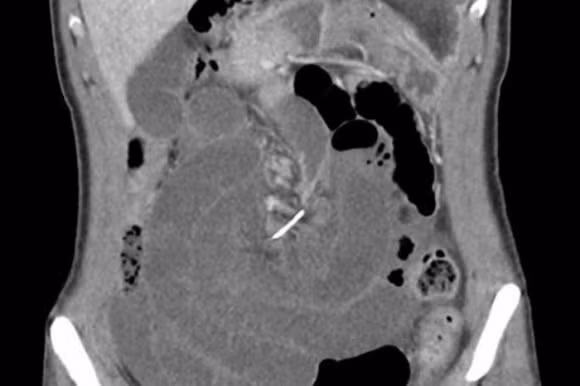

Một người phụ nữ 30 tuổi ở Úc đã phải nhập viện khi bị đau bụng dữ dội. Ban đầu, các bác sĩ chẩn đoán rằng, người phụ nữ này có thể có sỏi mật hoặc bị một mảnh xương cá chặn ngang ống mật. Tuy nhiên, kết quả chụp CT cho thấy một sợi dây kim loại mảnh dài 7cm đã đâm thủng ruột non của người bệnh ở nhiều chỗ. Do bị đâm vào nhiều chỗ, ruột non của người phụ nữ này đã bị xoắn xung quanh, gây ra hiện tượng được gọi là xoắn ruột non. Điều này cộng với nỗi đau cực độ mà người bệnh phải trải qua khiến các bác sĩ phải đưa ra quyết định là phẫu thuật.

niềng răng, tai nạn niềng răng, tai nạn niềng răng đáng sợ trên thế giới

Suốt 10 năm kể từ ngày niềng răng, người phụ nữ này không nhớ mình đã nuốt sợi dây kim loại hay mảnh kim loại nào ở chiếc niềng răng. Được biết, người phụ nữ sau đó đã hồi phục hoàn toàn sau ca cấp cứu và không gặp những tổn thương phụ khác.